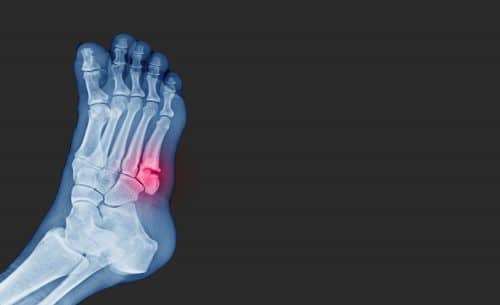

You have five metatarsal bones in each foot, spanning the length of the midfoot till the base of each toe.  A metatarsal fracture involves a complete or partial break of the metatarsal bone, and is a common foot injury.

How is a metatarsal fracture diagnosed?

Your doctor may suspect a metatarsal fracture if you have a history of recent trauma to the foot or ankle, or repeated foot stress, and present with some of the symptoms mentioned above, along with tenderness over the metatarsal on palpation.  The diagnosis can be confirmed by performing an X-ray, or sometimes an MRI scan, of your foot.